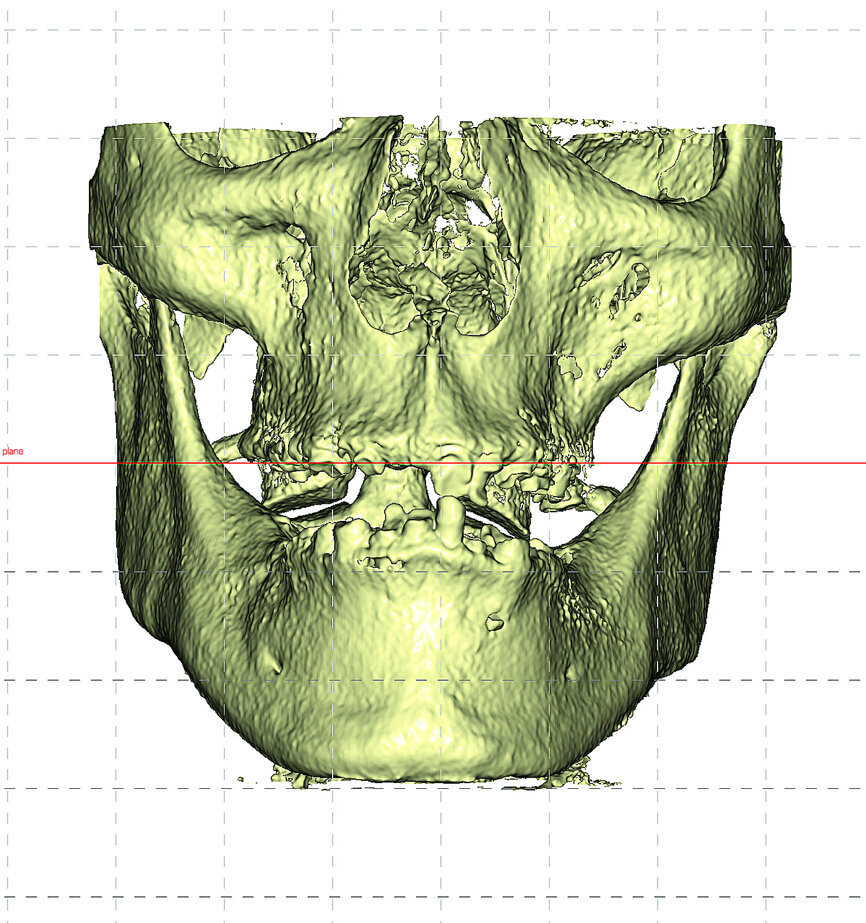

The diagnostic and treatment planning process using CBCT imaging provides for a variety of views including the axial, cross-sectional, panoramic, 3-D reconstructed volume (Fig. 2), and much more afforded with the use of interactive software as an aid to evaluating the thickness of the buccal plate, to assess the bone density, to visualise the trajectory of the tooth vs the bone, and then if a receptor site is found to be appropriate the clinician can position the implant to best support the desired restoration (Fig. 3).

Fig. 2: Frontal view of reconstructed volume from CBCT dataset allows for total inspection of the patient’s anatomy.

The initial review of the CBCT data was remarkable in the depiction of the thin, sharp, knife-edged alveolar ridge (Fig. 7). The 3-D volumetric reconstruction also reveals the position of the bilateral mental foramina and inferior alveolar nerves (seen in orange).

Contrary to the 2-D view of the panoramic radiograph, 3-D imaging and interactive treatment planning software allows clinicians to truly understand the patient's existing anatomy. For the example of the fully edentulous mandible, the CBCT scan revealed that the underlying bony ridge was quite sharp and uneven at the crest. This presentation would certainly not be favourable to place implants with a flapless surgical approach. In fact, to facilitate the placement of implants, and facilitate the restorative phase, it would be beneficial to flatten the irregular ridge to gain the appropriate and desired width at the alveolar crest (Fig. 8).